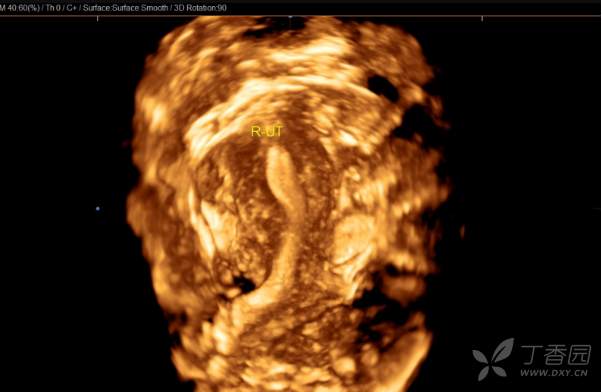

简要病史:此次患者来我院求医是因2020年12月右侧宫腔胚胎移植失败,生殖科考虑患者左侧宫腔条件比右侧宫腔要好,但多次宫腔镜未能探入左侧宫腔,B超提示左侧子宫内膜厚,回声不均(未见单),建议宫腔镜。阴道三维彩超:两个子宫大小分别为5.0×4.6×3.6cm(左侧 ),4.8×4.2×3.1cm(右侧 ),横切面宫底部为蝶状,宫体部横径增宽,可见两个宫腔内膜回声,左侧厚约1.0cm,回声不均匀,右侧厚约0.6cm,宫颈部呈哑铃状。复查彩超:双子宫,右侧宫腔内膜厚0.5cm,左侧宫腔内可见分离暗区,左侧子宫下段部分内膜中断,该处至宫颈外口长约4cm的范围内未见内膜回声。